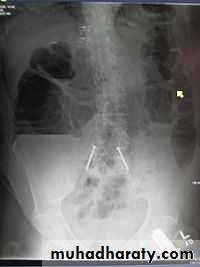

Small bowel obstruction

Large bowel obstruction

Valvulae conniventes

Present

Absent

Number of loops

Many

Few

Distribution of loops

Central

Peripheral

Haustra

Diameter

3 – 5 cm

More than 5 cm

Radius of curvature

Small

Large

Fecal material

4

Causes of bowel dilatation

• Mechanical SB obstruction : small bowel dilation with normal or reduced caliber of colon• Mechanical LB obstruction: dilated colon down to the point of obstruction. May be accompanied by small bowel dilation if the ileocecal valve becomes incompetent

• Generalized paralytic ileus: SB and LB dilatation, gas may be present in the rectum